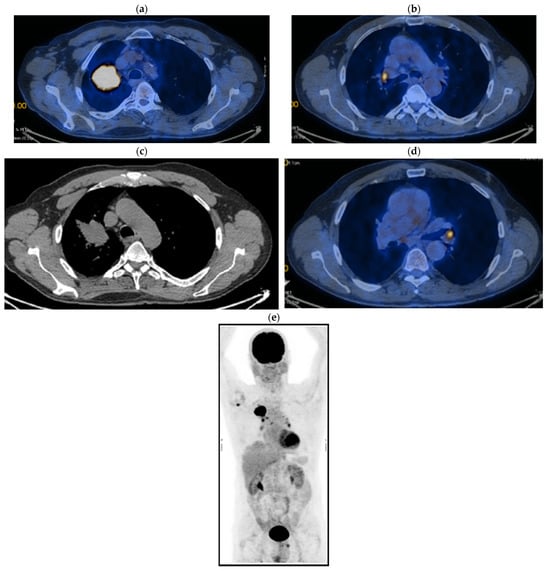

2. Case Presentation

2.2. Monitoring 2022: Oncological Commission 1910/16.08.2022

2.3. Oncological Committee 07/25/2023 Recommended

- Consider rescue re-irradiation (SBRT), taking into account the current primary tumor dimensions of 24 × 34.2 mm on PET CT from 06/2023 and also the total dose previously administered (08–09/2020), the previously applied fractionation, the time between the two irradiations, the cellular repair time and the dose constraints for the organs at risk.